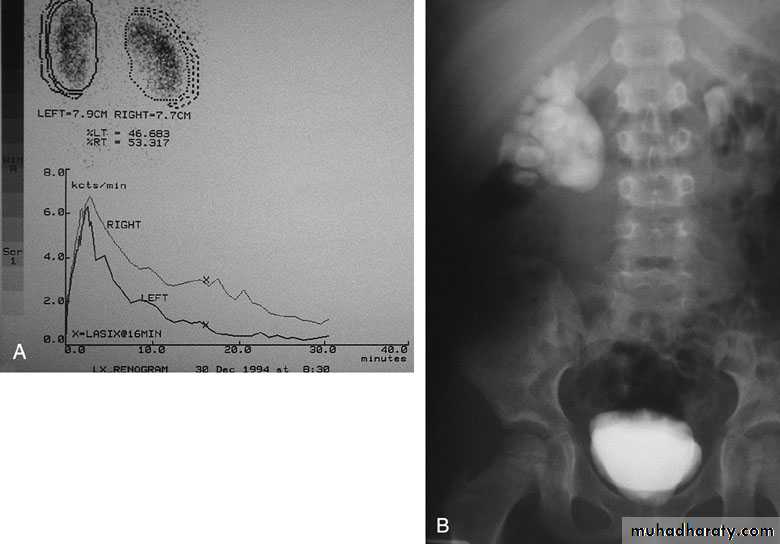

U/S: hydronephrosisIVU: diagnostic , hydronephrosis with fixed stenotic segment or complete obstruction

CT scan: hydronephrosis that ends abruptly

Radionuclide Renography: to see the split function of each kidneyPressure-Flow Studies : Whitaker test